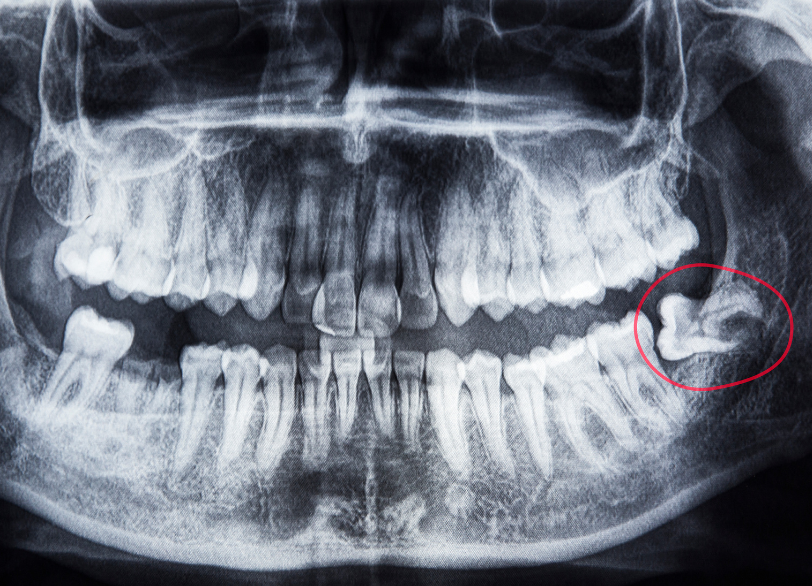

親知らず(第三大臼歯)は、奥歯のさらに奥に生える歯で、多くの場合、正しい位置に生えないことがあります。

その結果、歯茎や周囲の組織に影響を及ぼし、以下のような問題が発生することがあります。

- 隣接歯への負担

斜めに生えることで隣の歯を圧迫 - 歯茎の炎症

食べ物の詰まりや細菌の繁殖による炎症 - 痛みや腫れ

感染症が広がることで引き起こされる痛み

親知らずの状態により、抜歯が必要となるケースやそのまま保存が可能な場合があります。